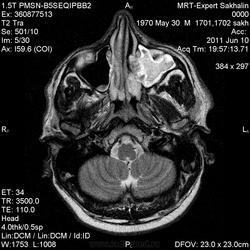

Мужчина обратился к нам без направления.Жалобы на головную боль( он не совсем русский, поэтому плохо понимал вопросы, соответственно и не знал, как на них ответить)- в общем жалобы смутные и непонятные.

Провели исследование.Что скажете, уважаемые коллеги

Выраженное утолщение слизистой оболочки левой верхнечелюстной пазухи, полость пазухи полностью выполнена жидкостным содержимым, что нарушает ее пневматизацию. Через сквозной дефект кортикальных пластинок медиальной стенки верхнечелюстной пазухи процесс распространяется в левуюю половину носовой полости. А отсутствие левой среднией носовой раковины в сочетании с вышеуказанным дефектом стеки наводит на мысль об оперативном вмешательстве (конхиотомия?) в анамнезе, либо это последствия далеко зашедшего хронического воспаления.

Stanislava, спасибо за коммент. По поводу вмешательства-пациента активно "пытали", но все отрицает.Первая мысль была об об"еме, сейчас думаю о полипозе.Хотя первая мысль пока в силе.Жаль, что мы не всегда можем проследить  дальнейшую судьбу пациентов.

Тогда деструкция в результате хронизации процесса. Есть еще вариант травмы с повреждением стенок пазухи. А полипоз - это реактивное разрастание слизистой, с множеством полипов, для которых характерно локализация сразу в нескольких пазухах. У вашего пациента довольно равномерное утолщение слизистой оболочки толки одной пазухи. А вот об объемном процессе я вообще не думаю. Если Вас смущает накопление контраста то оно должно там быт, это ведь слизистая, а она очень васкуляризированна.

Мне кажется не она - на исходных снимках процесс идет из пазухи

Валентин Львович, на эстезионейробластому это совсем не похоже. Распространения процесса в полость черепа нет, да и решечтатая пазуха, в общем-то, не вовлечена.

У парня полипы верхнечелюстной пазухи с распространением в средний носовой ход, отсюда нарушение вентиляции пазухи и гайморит. Деструкции раковины там нет, есть атрофия от давления. На КТ эти изменения костной ткани обычно лучше видны.